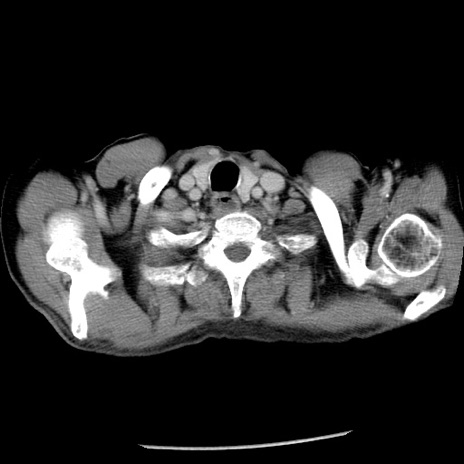

症例26(横断像)

【症例】80歳代男性

【主訴】嘔吐

【現病歴】昨晩2回嘔吐あり、今朝になっても嘔吐あり。来院。

【既往歴】胃潰瘍

【身体所見】意識清明、BT 37.6℃、BP 166/95mmHg、HR 100bpm、SpO2 97%、腹部:平坦・軟、腸蠕動音聴取良好、圧痛なし。

【データ】WBC 21900、CRP 1.46